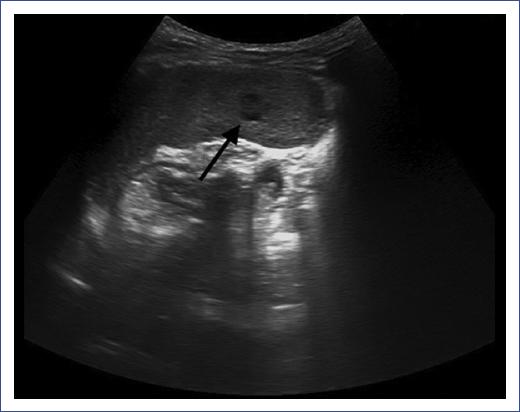

Two days later (10 days after the fever started), the patient presented abdominal pain. The patient had referred pain in the right hypochondrium upon palpation with no signs of abdominal resistance. The rest of the physical examination was completely normal (no hepatosplenomegaly and no lymph nodes were detected). Another blood test was done with similar results: WBC 12.960x103/mm3 (neutrophil 8.280x103/mm3, lymphocytes 3.710x103/mm3, monocytes 650x103/mm3) and CRP 64.87 mg/L. An abdominal ultrasound was requested because of the localized pain. The results showed hepatic and splenic hypoechoic lesions without hepatosplenomegaly (Figures 1 and 2). The size of the liver and the spleen were 10 cm and 8 cm, respectively, both normal for the patient's age.

Figure 2 Spleen ultrasound with hypoechoic lesions. Abdominal ultrasound of a 5-year-old male with splenic hypoechoic, not anechoic, lesions. No sign of blood flow after assessment with Doppler ultrasound is noticed. The lesions have a maximum size of 4 mm. The spleen has normal size.

Micro-abscesses in the liver or spleen can be detected in more than 50% of patients with hepatosplenic CSD through abdominal imaging studies17. Multiple hepatosplenic lesions are usually small, round, and hypodense on computerized tomography and result from granulomas, abscesses, or lymphoplasmacytic inflammation13.

In this case, hepatosplenic lesion diagnosis was performed by ultrasound and the spondylitis of the D6 vertebra by MRI.